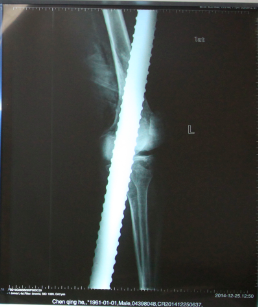

经了解,伤者陈某为河南进京打工人员,当天上午在花乡一建筑工地的电梯井里干活,突然,一根长近2米、直径近4厘米钢筋从20多米高空落下,当场击中了正在地下室作业的陈某,钢筋从陈某的左膝关节外侧斜穿至左小腿内侧,和他同在地下室干活的工友等紧急送往北京积水潭医院。

北京积水潭医院急诊的大夫和护士迅速对病人进行抢救,心电监护,开放静脉,并将患者左腿上的裤子小心翼翼的剪开。创伤骨科孙旭大夫和手外科童德迪、薛云浩大夫一边了解病人的情况,一边给病人进行检查,病人左脚没有知觉,怀疑至少有一根神经有损伤,为判断是否有骨折,拍了X光片子。

麻醉成功后,手外科童德迪医生慢慢将钢筋拔出,钢筋从膝关节穿过去,股骨下端和胫骨都劈断了,因伤势严重,术中要探查和修补血管和神经,最后上外固定架,手术进行了2个多小时,经过全体医护人员的努力,病人救治成功。

X光片